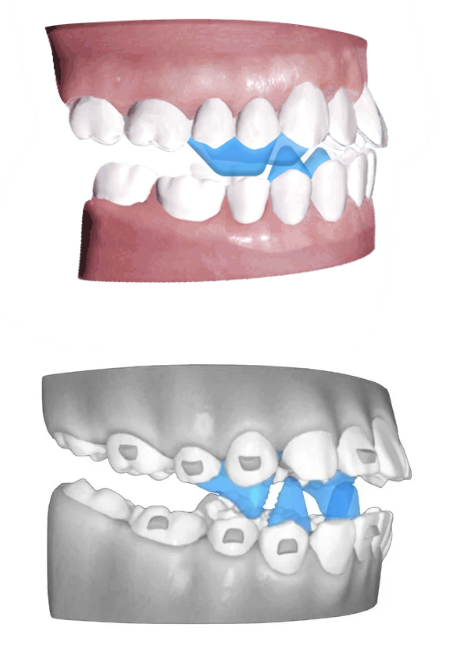

Product pictures A6